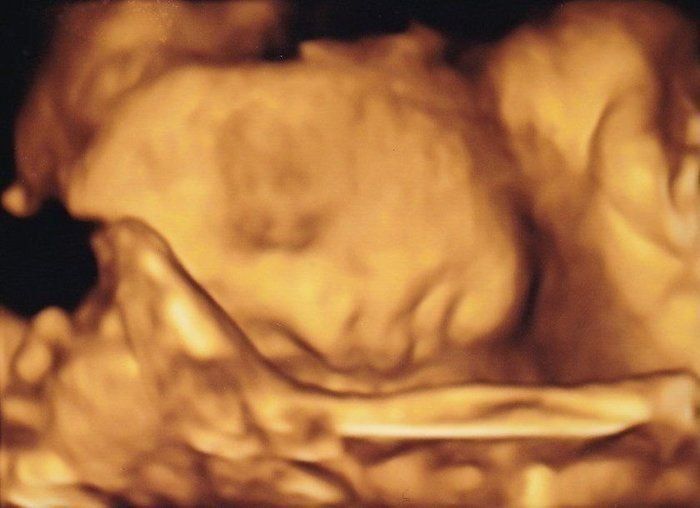

かえるさんの妊娠28週目のエコー写真

顔が見えました。3Dの撮影も行いました。いまだに娘の寝顔はおなかの中にいた時みたいな顔です。想像よりも骨太なイメージで、推定体重も大きめ。体調の良い日に意を決して渋谷に出かけ、0歳児を連れたママ達が買い物をしている姿を見てまぶしく感じました。「私も来年はあんな風にたくましくなっていますように」と願いました。

お顔をアップにした4D画像です。うつむき加減で眠っているように見えました。赤ちゃんは順調に大きくなり、これ以降、毎回「ちょっと大きめですね」と言われるようになります。実際、おなかも苦しくなってきて、パソコン作業がつらくなってきました。ちょうど真夏の時期で、外出がとてもつらかったのを覚えています。